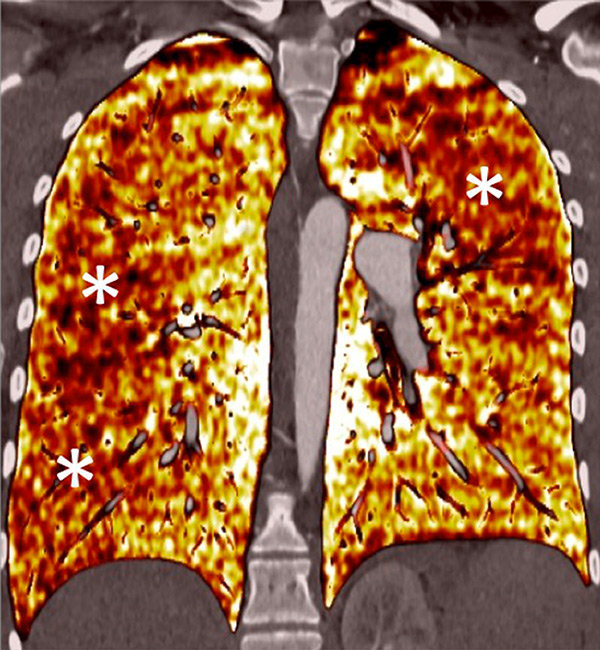

Figure 6

Perfusion heterogeneities in idiopathic pulmonary artery hypertension (stars) in two different patients (A/B). The dilatation of the arteries in pulmonary hypertension (arrows) is not always observed depending on the severity of pulmonary hypertension.